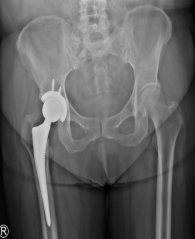

初次手术后3周左右,患者情况已逐渐恢复良好,何罕亮医师团队再次针对陈女士的股骨颈骨折实施了“全髋关节置换术”。全髋关节置换术是用人工关节来替换病变的髋关节,适用于65岁以上股骨颈骨折的患者。整个手术1小时即完成,手术出血不到200ml。

全髋关节置换术后X线